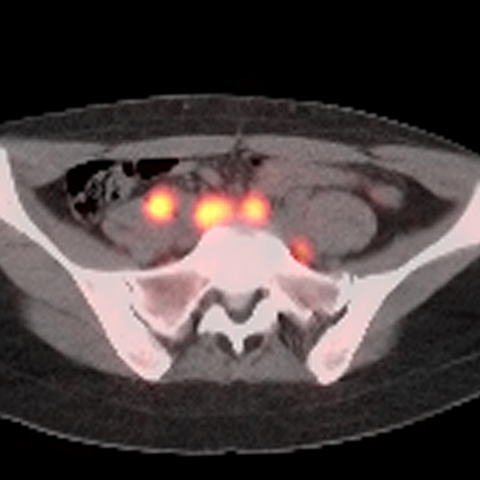

40 year old male presents with lymphadenopathy and unexpected weight loss [2 of 4]